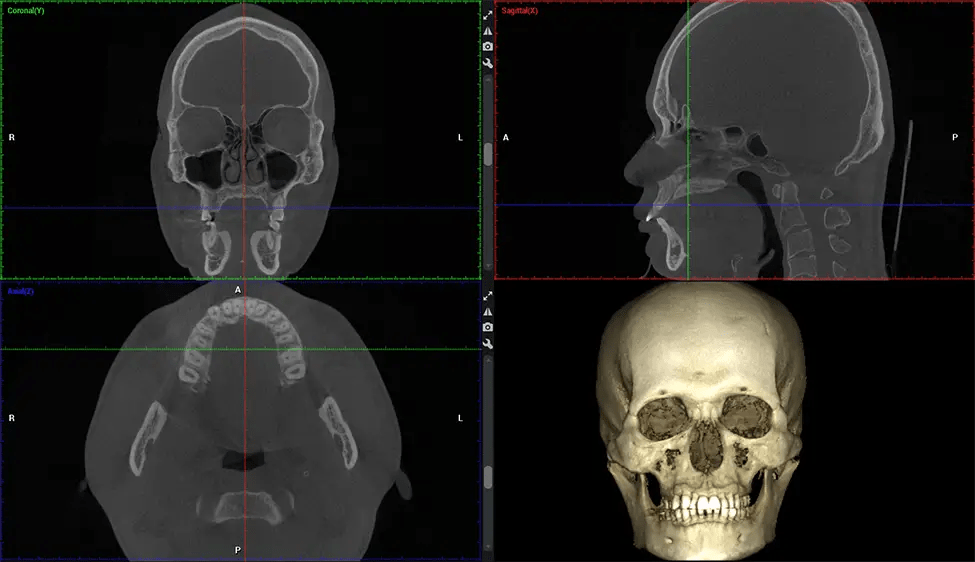

Cone Beam Computed Tomography (CBCT) is an advanced imaging technique used in dentistry and maxillofacial surgery to obtain detailed 3D images of the oral and maxillofacial structures. At Dr G Dental Studio, our CBCT scanners utilize a cone-shaped X-ray beam and a specialized detector to capture images from different angles. A computer then combines these images to create a 3D representation of the patient’s oral anatomy.

This 3D scan, called cone beam computed tomography, gives your dentist a more complete image of your oral anatomy and disease processes than a traditional X-ray. Unlike conventional X-rays, which capture a 2D image of your mouth from various angles, a 3D scan takes multiple digital X-rays for one image. It provides a complete view of your jaw, teeth, nerves, and soft tissues. This enhanced view allows dentists to detect minor issues not visible in traditional 2D scans, such as impacted wisdom teeth or bone fractures in the sinus cavity.

The patient is first positioned in the CBCT scanner, which typically consists of a rotating arm that houses the X-ray source and a detector. The patient’s head is immobilized to ensure accurate image capture. The X-ray source and detector rotate around the patient’s head, capturing various X-ray images from multiple angles. As the X-ray source rotates, it emits the cone-shaped X-ray beam towards the detector. The detector captures the X-ray images, which are then processed by the CBCT software.

After the scanning process, the captured X-ray images are processed by the CBCT software, which applies algorithms to reconstruct a detailed 3D image of the scanned area. The software compiles these individual X-ray images and creates a digital 3D representation of the patient’s anatomy. The reconstructed 3D CBCT image can be viewed and analyzed by the dentist or radiologist. This image can be manipulated, rotated, and zoomed in or out to examine specific structures and evaluate the patient’s condition.